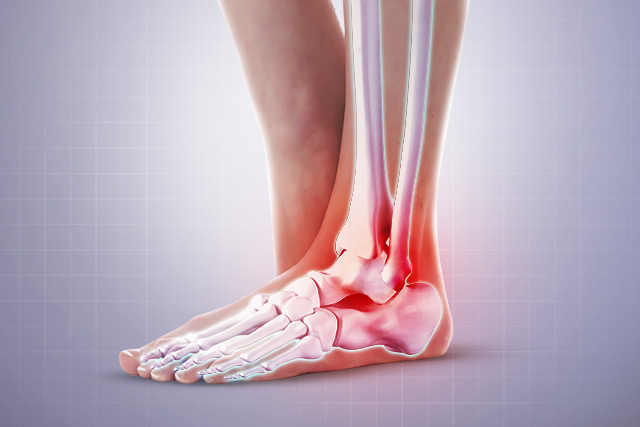

6. 발꿈치에 붓기

족저 근막염이 악화되면 발꿈치가 부풀어 오를 수 있습니다. 염증이 생기면서 발꿈치의 부기가 동반될 수 있습니다. 붓기는 보통 서 있거나 걷고 나서 더 뚜렷하게 나타납니다.

족저 근막염 증상 7. 자주 발생하는 발목 통증

족저 근막염이 있으면 발목에도 통증이 발생할 수 있습니다. 이는 발바닥의 과도한 긴장으로 인해 발목에 추가적인 부담이 가기 때문입니다.